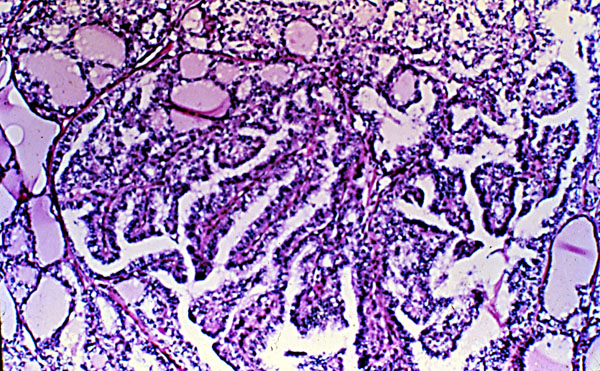

Papillary carcinoma, micro,thyroid

This photomicrograph shows well-differentiated papillae with hyperchromatic surface epithelial cells, and no capsular separation of tumor cells from adjacent normal thyroid follicles.